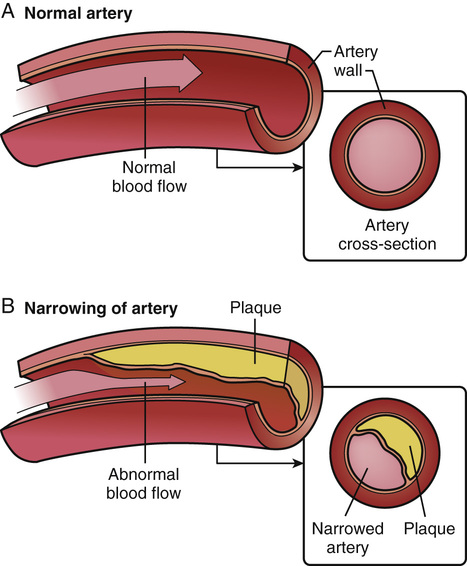

A typical blood vessel. ( a ) shows a normal artery with normal blood …

Normal Artery And Unhealthy Artery Stock Vector – Image: 52223409